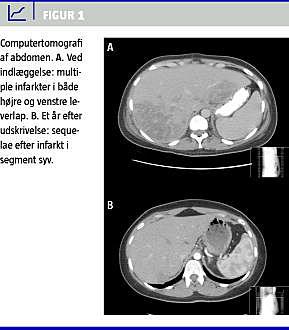

En 29-årig kvinde, der var i 21. gestationsuge, blev indlagt på en gynækologisk afdeling med abdominalia og febrilia. Fem dage forinden havde hun haft diarré, kvalme og opkastninger i to døgn. I forbindelse med en dyb venetrombose ni år tidligere havde hun fået diagnosticeret primær APS, hvorfor hun var i profylaktisk behandling med lavmolekylært heparin. Ved indlæggelsen påbegyndte man bredspektret antibiotikabehandling, og patientens heparindosis blev fordoblet. Der blev foretaget medicinsk abort med fødsel af et vækstretarderet foster, og efterfølgende blev der foretaget abrasio på grund af retineret væv. Klinisk og paraklinisk forværredes tilstanden, og patienten blev på tredje indlæggelsesdag overflyttet til en gastroenterologisk specialafdeling. Her blev der ved computertomografi påvist multiple leverinfarkter, vena portae-trombose samt bilaterale pleuraeksudater. Der var ikke tegn på Budd-Chiaris syndrom (Figur 1 ). Gennem de parakliniske fund bekræftede man HELLP-syndrom. Der sås hæmolyse med laktatdehydrogenase over 2.500 U/l, forhøjede levertal med alanintransaminase på over 5.000 U/l, samt trombocytopeni på 22 × 109 /l. Desuden sås der tegn på begyndende leversvigt i form af fald i koagulationsfaktoren (2, 7, 10) til 0,32 internationale enheder (IE) (Tabel 1 ). Der blev startet infusion med magnesiumsulfat. På fjerde indlæggelsesdag blev højdosissteroid initieret, og i det sjette døgn blev der substitueret med antitrombin. Herefter bedredes tilstanden, og patienten blev udskrevet en måned senere med normale levertal. Koagulationsfaktoren (2, 7, 10) forblev nedsat ved udskrivelsen på grund af behandling med vitamin K-antagonist. Ved kontrolskanning et år senere påvistes sequelae efter infarkt i segment syv (Figur 1).